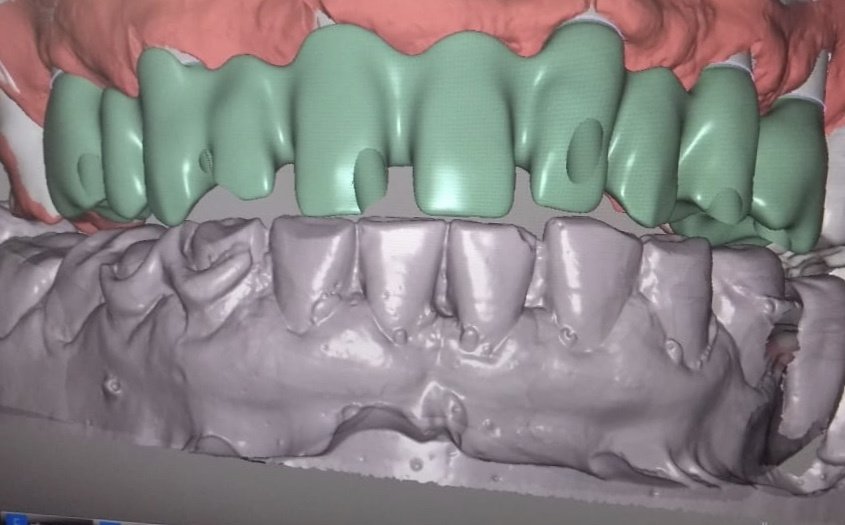

About Live Implants Nicaragua Virgil Mongalo DMD is a dental implant surgeon, past professor of implant surgeries at the University of Miami and the University of Florida has opened a surgical implant center in Managua. This is a state of the art facility consisting of equipped with Ct-scan, 3D Printer, zirconia milling machine, 8 surgical rooms, and USA sterilization controls. His team consists of implant surgeries professor accredited... (Show more)